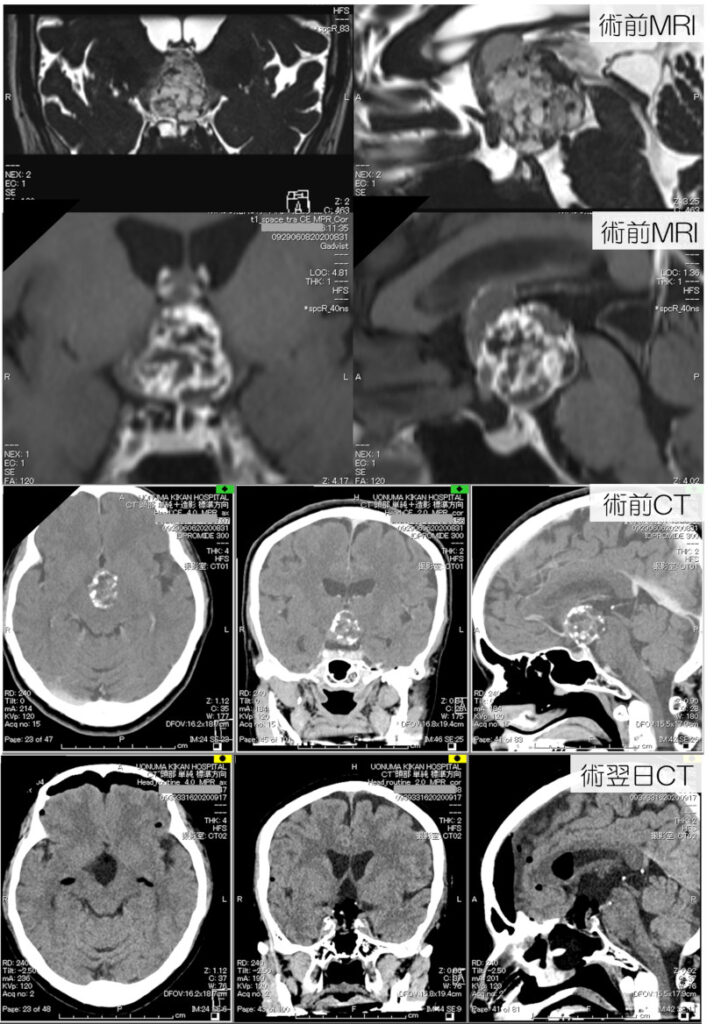

頭蓋咽頭腫

頭蓋咽頭腫も、経鼻摘出されるようになってきております。従来は開頭手術を要しましたが、下垂体腺腫摘出の応用・発展として、これらを経鼻的に摘出出来るようになってきております。経鼻手術の術式の適応は、術前評価により適切に判断する必要があります。